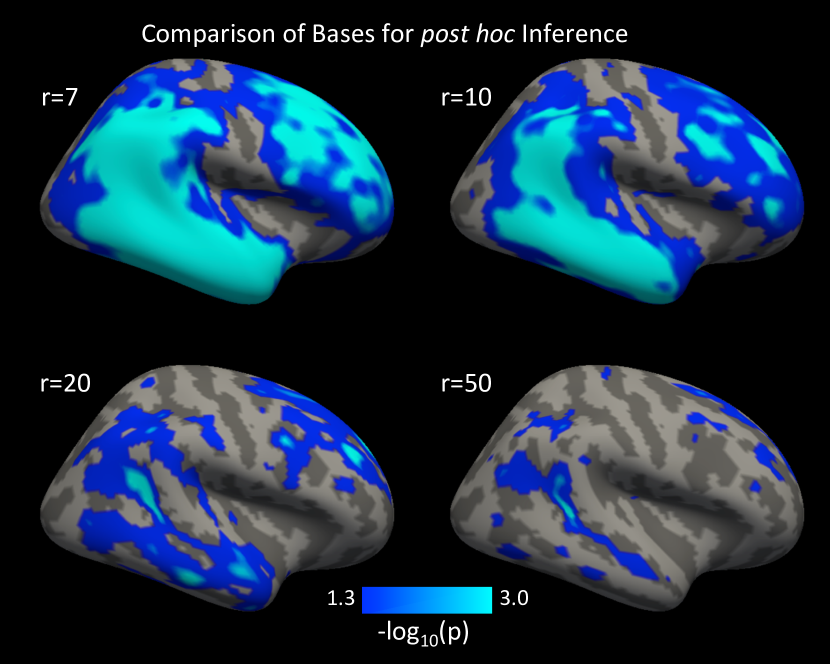

To demonstrate the impact of the choice of , we performed post hoc inference on the scores for 4 different PCA bases (Figure 2). It is clear from Figure 2 that increasing the dimension of the basis increases the spatial specificity of the results. However, the larger bases also come with the cost of reduced power due to the larger degrees of freedom of the basis. This is also illustrated in Table 2, where the larger bases have a higher rejection threshold.